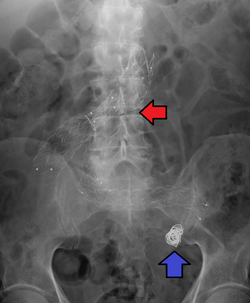

Abdominal aorta size classification

Ectatic or mild dilatation |

>2.0 cm and <3.0 cm[14]

|

| Moderate |

3.0–5.0 cm[14]

| Large or severe |

>5.0[14] or 5.5[15] cm

Abdominal aortic aneurysms are commonly divided according to their size and symptomatology. An aneurysm is usually defined as an outer aortic diameter over 3 cm (normal diameter of the aorta is around 2 cm),[16] or more than 50% of normal diameter that of a healthy individual of the same sex and age.[9][17] If the outer diameter exceeds 5.5 cm, the aneurysm is considered to be large.[15]